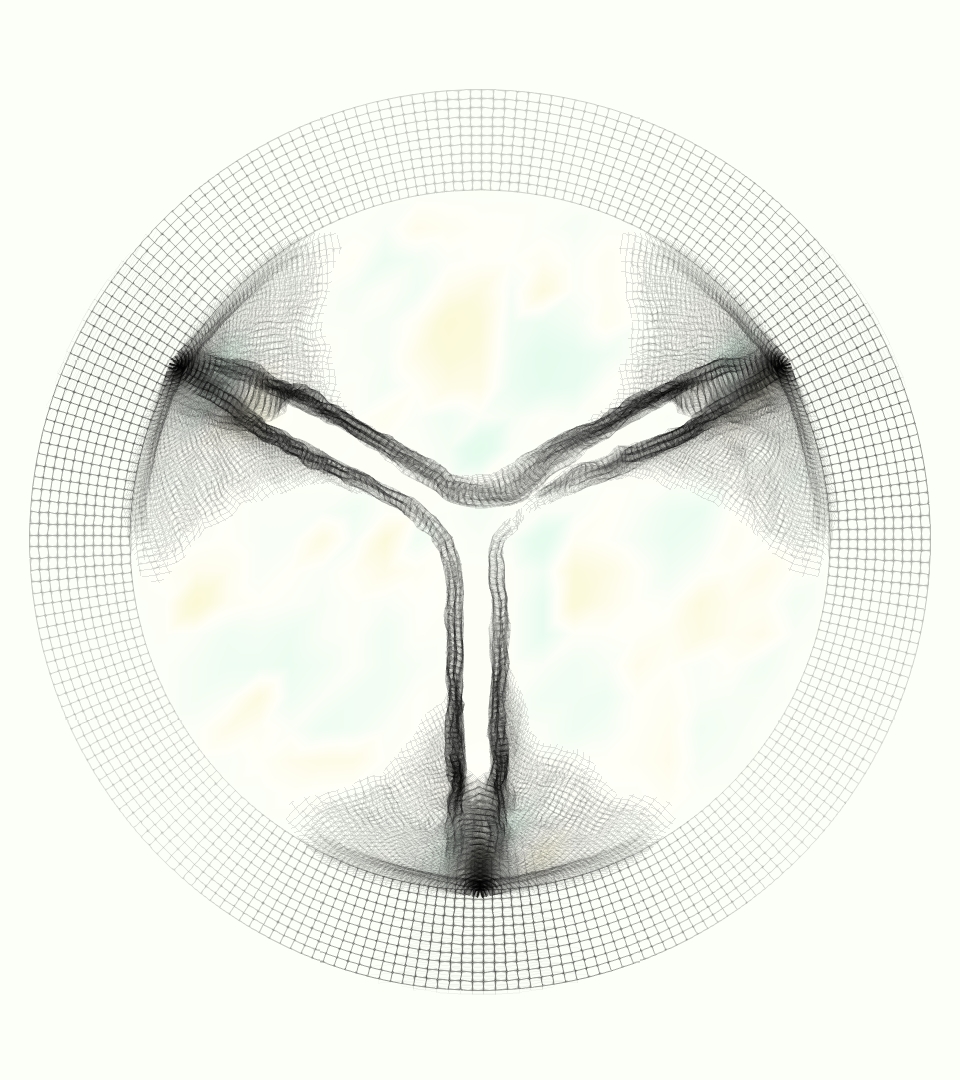

The emergent hemodynamics showed excellent qualitative agreement with experiments. Slice views of the axial component of fluid velocity ( component) in the sagittal plane that cuts through the center of the vessel, parallel to the flow direction, are shown in Figure 5. The flow in both the simulation and the experiment began to accelerate at the same time, with a jet forming through the open valve leaflets. The velocity, angle, and shape of the jet agreed well between the two cases during systole. The simulation captured the slight upward angle of the jet, which was not fully centered in the vessel. It also matched the location where the jet impacts the wall and the slower speed of the jet as it turns with the MPA downstream. As the flow decelerated, the fluid along the interior curve of the vessel reversed first while forward flow persisted where the jet was strongest, as seen in both the simulation and experimental results.

In both the experiment and the simulation, a separation region of reverse flow developed along the interior curve of the vessel under the core jet through the valve. The reverse flow began to develop at the same time in the cardiac cycle and grows throughout systole. The simulation lacked reversed flow in the entire region where reversed flow was present in the experiment, but this region developed some flow separation and had much slower flow than elsewhere in the vessel. Thus, the simulation captured that this is a distinct region from the core jet through the valve opening. There was a smaller amount of slower and slightly reversed flow along the outer curve of the vessel, close to the valve annulus and scaffold support. This region was well-matched between the experiment and the simulation.

Slice views of the (axial) component of fluid velocity in the axial plane, orthogonal to the flow direction, show that the simulation replicated the development of the jet over the cardiac cycle. At each phase, the simulation matched the forward speed of the core of the jet and the locations of reverse flow back towards the valve annulus. While there are some differences in the shape of the jet at certain phases and locations, the simulation clearly produced the general dynamics of the cardiac cycle that are seen in the experiment.

At = 0, the axial slice directly at the valve annulus shown in columns 1 and 2 in Figure 6, there was excellent agreement between the simulation and experiment over the cardiac cycle in the speed and shape of the jet through the valve. In both cases, the axial velocity increased as the flow accelerated during systole and the valve leaflets opened, then decreased during diastole with slight negative velocity before the valve leaflets were fully closed. The forward flow through the valve annulus did not form a full circle, but rather developed a triangular shape with a point of the triangle forming along the interior curve of the vessel, at the bottom of the axial slices. At = 0, the points of this triangular jet shape aligned with the commissures of the valve. This shape persisted during peak systole and was well-matched by the simulation.

The axial slice = 0.625 cm, shown in columns 3 and 4 in Figure 6, cut through the support scaffolding of the valve and the leaflets when they are open. In the experimental data, the shape of the jet changed as it moved downstream. A triangular shape occurred, but the points were then aligned with the middle of each open leaflet as opposed to the commissures. Those points were also more rounded than they were at = 0. The peak velocity of the jet was faster at = 0.625 cm than at = 0, as the flow accelerated through the open valve leaflets. The simulation produced these features at = 0.625 cm. The triangular shape of the jet shifted similarly, and its speed increased compared to the upstream slice. As the flow decelerated into diastole, the jet shape remained roughly triangular but diminished in intensity before disappearing after valve closure.

The jet continued to develop at = 1.25 cm, an axial slice immediately downstream of the valve scaffolding and open leaflets, shown in columns 5 and 6 in Figure 6. In the experimental data, the points of the triangular jet shape extended further towards the vessel wall. In addition, regions of reversed flow developed in the locations downstream of the commissures, resulting in curved sides to the shape of the jet. Each tip of the jet was unique, due to variations in the individual leaflets in the physical bioprosthetic valve. These variations are apparent in the velocity fields, possibly because the jet edges are similar enough cycle to cycle that irregularities are still being captured even with phase averaging. Further discussion of these features can be found in Schiavone et al. [39], which showed that the jet tip shapes occurred in different pulmonary anatomies, demonstrating that they were likely due to inherent properties of each leaflet. The leaflets in the mathematical model of the valve are identical, so these nuances in leaflet variation could not be replicated. The simulation did capture some of the extension of the tips of the jet, as they were closer to vessel wall at slice = 1.25 cm than = 0.625 cm. The curves in the triangular sides of the jet were also present in the simulation, though they were less pronounced than the experimental data. At both = 0.625 cm and = 1.25 cm, the jet shape in the simulation was smoother than the jet in experiment. It is possible that the free edges of the leaflets in the mathematical model are not fully replicating the behavior of the physical leaflets of the bioprosthetic valve, in particular the amplitude or frequency of leaflet flutter, leading to the variations seen in the jet shape at = 1.25 cm downstream of the leaflet edges. The simulation, however, does capture the key features of the triangular shape and speed of the jet. Overall, qualitative comparisons demonstrated that the simulation reproduced key features of the flow during systole and diastole.